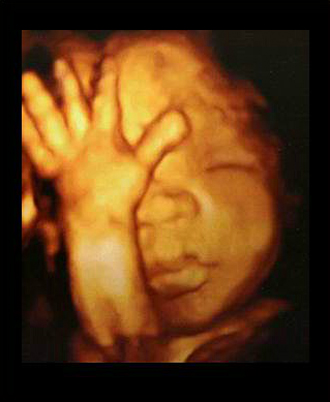

- 4차원 후기 정밀 초음파 (26~28주)